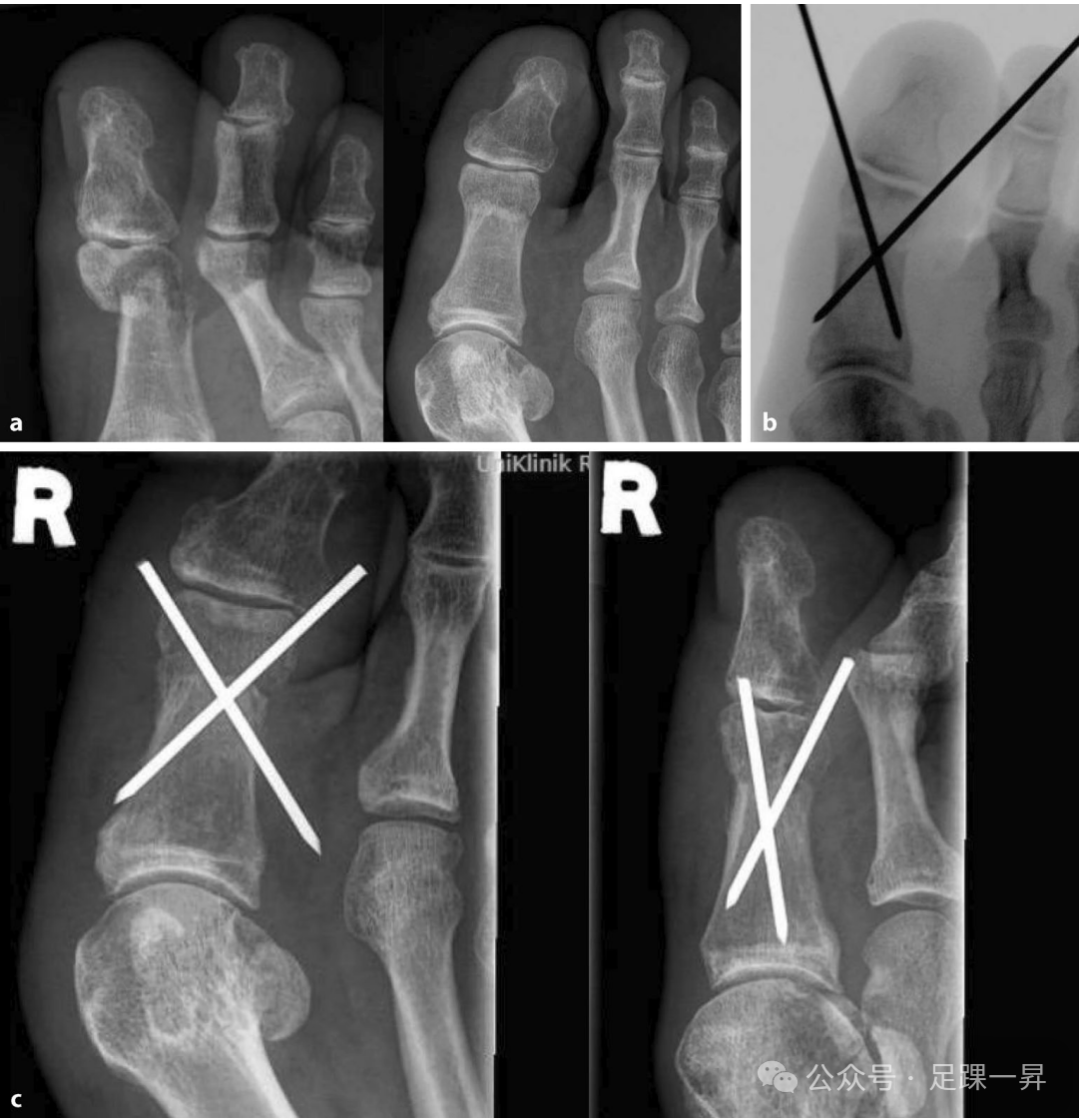

▲图示**趾近端趾骨干骺端骨折。通过闭合复位撬拨技术联合经皮克氏针固定进行手术治疗。a 术前X线片;b 术中影像学检查;c 术后2周X线随访检查。